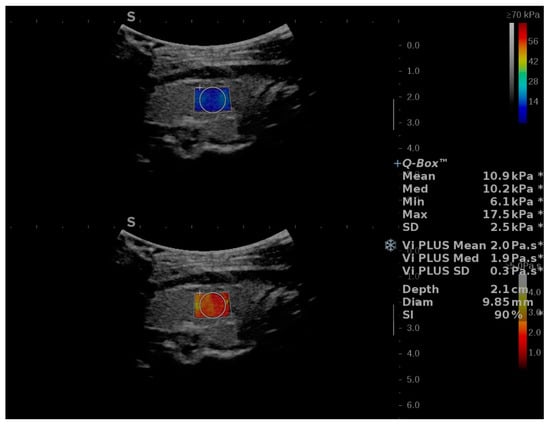

2.2. Two-Dimensional SWE PLUS and Viscosity PLUS Measurements